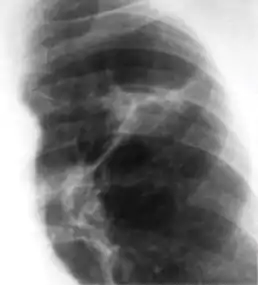

In countries where cow milk infected with Mycobacterium bovis has been eliminated (due to culling of infected cows and pasteurization), primary tuberculosis is usually caused by Mycobacterium tuberculosis and almost always begins in the lungs. Typically, the inhaled bacilli implant in the distal airspaces of the lower part of the upper lobe or the upper part of the lower lobe, usually close to the pleura. As sensitization develops, a 1- to 1.5-cm area of gray-white inflammation with consolidation emerges, known as the Ghon focus. In most cases, the center of this focus undergoes caseous necrosis. Tubercle bacilli, either free or within phagocytes, drain to the regional nodes, which also often caseate. This combination of parenchymal lung lesion and nodal involvement is referred to as the Ghon complex. During the first few weeks, there is also lymphatic and hematogenous dissemination to other parts of the body.

The Ghon complex undergoes progressive fibrosis, often followed by radiologically detectable calcification (Ranke complex), and despite seeding of other organs, no lesions develop. Although they are often confused, Ranke complex and Ghon complex are not synonymous. The Ranke complex is an evolution of the Ghon complex (resulting from further healing and calcification of the lesion).[4][5]